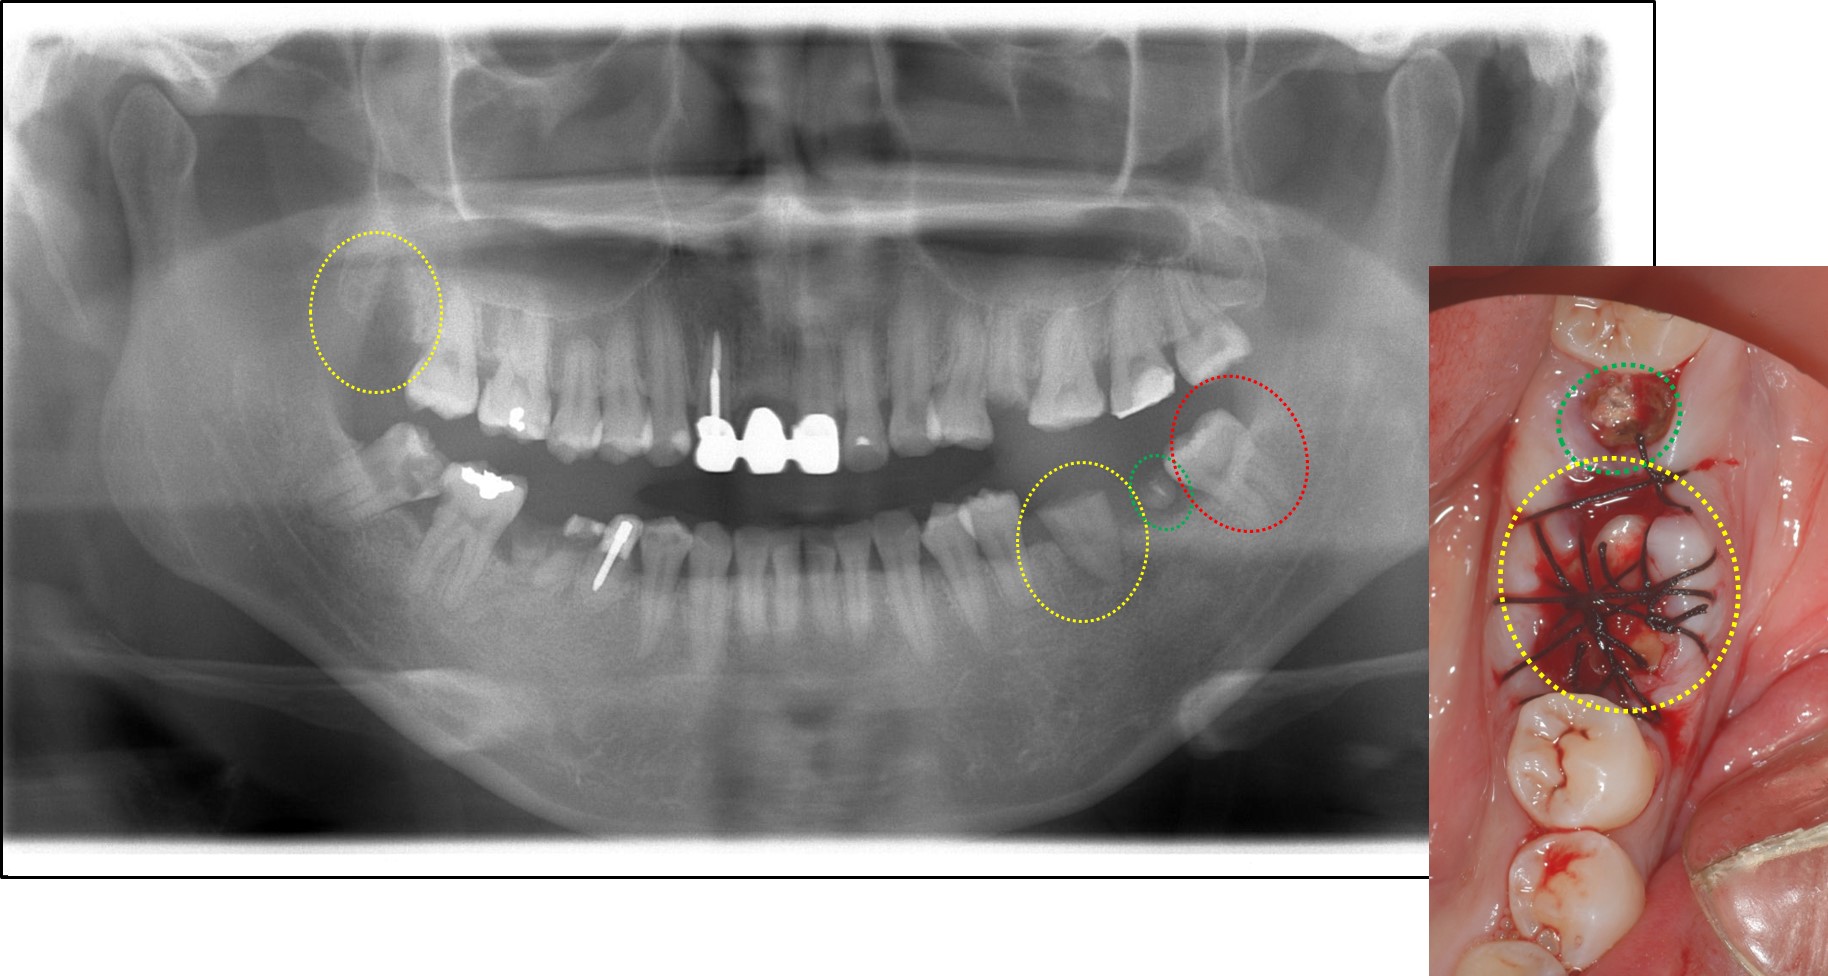

まず下写真からご覧ください。

青〇と緑〇の歯は根だけの状態になっており抜歯する必要があります。

そこで、黄色〇(親知らず)を抜歯して青〇部分に移植する計画としました。

下写真をご覧ください。

黄色〇(親知らず)を移植したレントゲン写真と移植後に縫合した口腔内写真になります。緑〇の歯は後日抜歯しました。